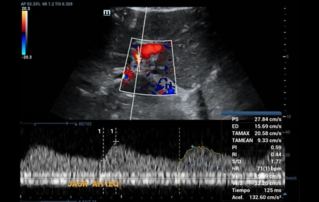

![evaluate-liver-graft-contrasted-ultrasound.thumb.319.319 Ultrasound Journal 37 - Evaluation of liver graft by contrasted ultrasound and variables that may alter normality]() Ultrasound Journal 37 - Evaluation of liver graft by contrasted ultrasound and variables that may alter normalityDiscover how Mindray Resona R9 with Chrono-Parametric Mode CEUS revolutionizes post-liver transplant monitoring, enabling early detection of vascular complications and standardized perfusion assessment.Ultrasound Cases | Ultrasound | Smart applications | Digitalization | General imaging 2025-08-11

Ultrasound Journal 37 - Evaluation of liver graft by contrasted ultrasound and variables that may alter normalityDiscover how Mindray Resona R9 with Chrono-Parametric Mode CEUS revolutionizes post-liver transplant monitoring, enabling early detection of vascular complications and standardized perfusion assessment.Ultrasound Cases | Ultrasound | Smart applications | Digitalization | General imaging 2025-08-11 -